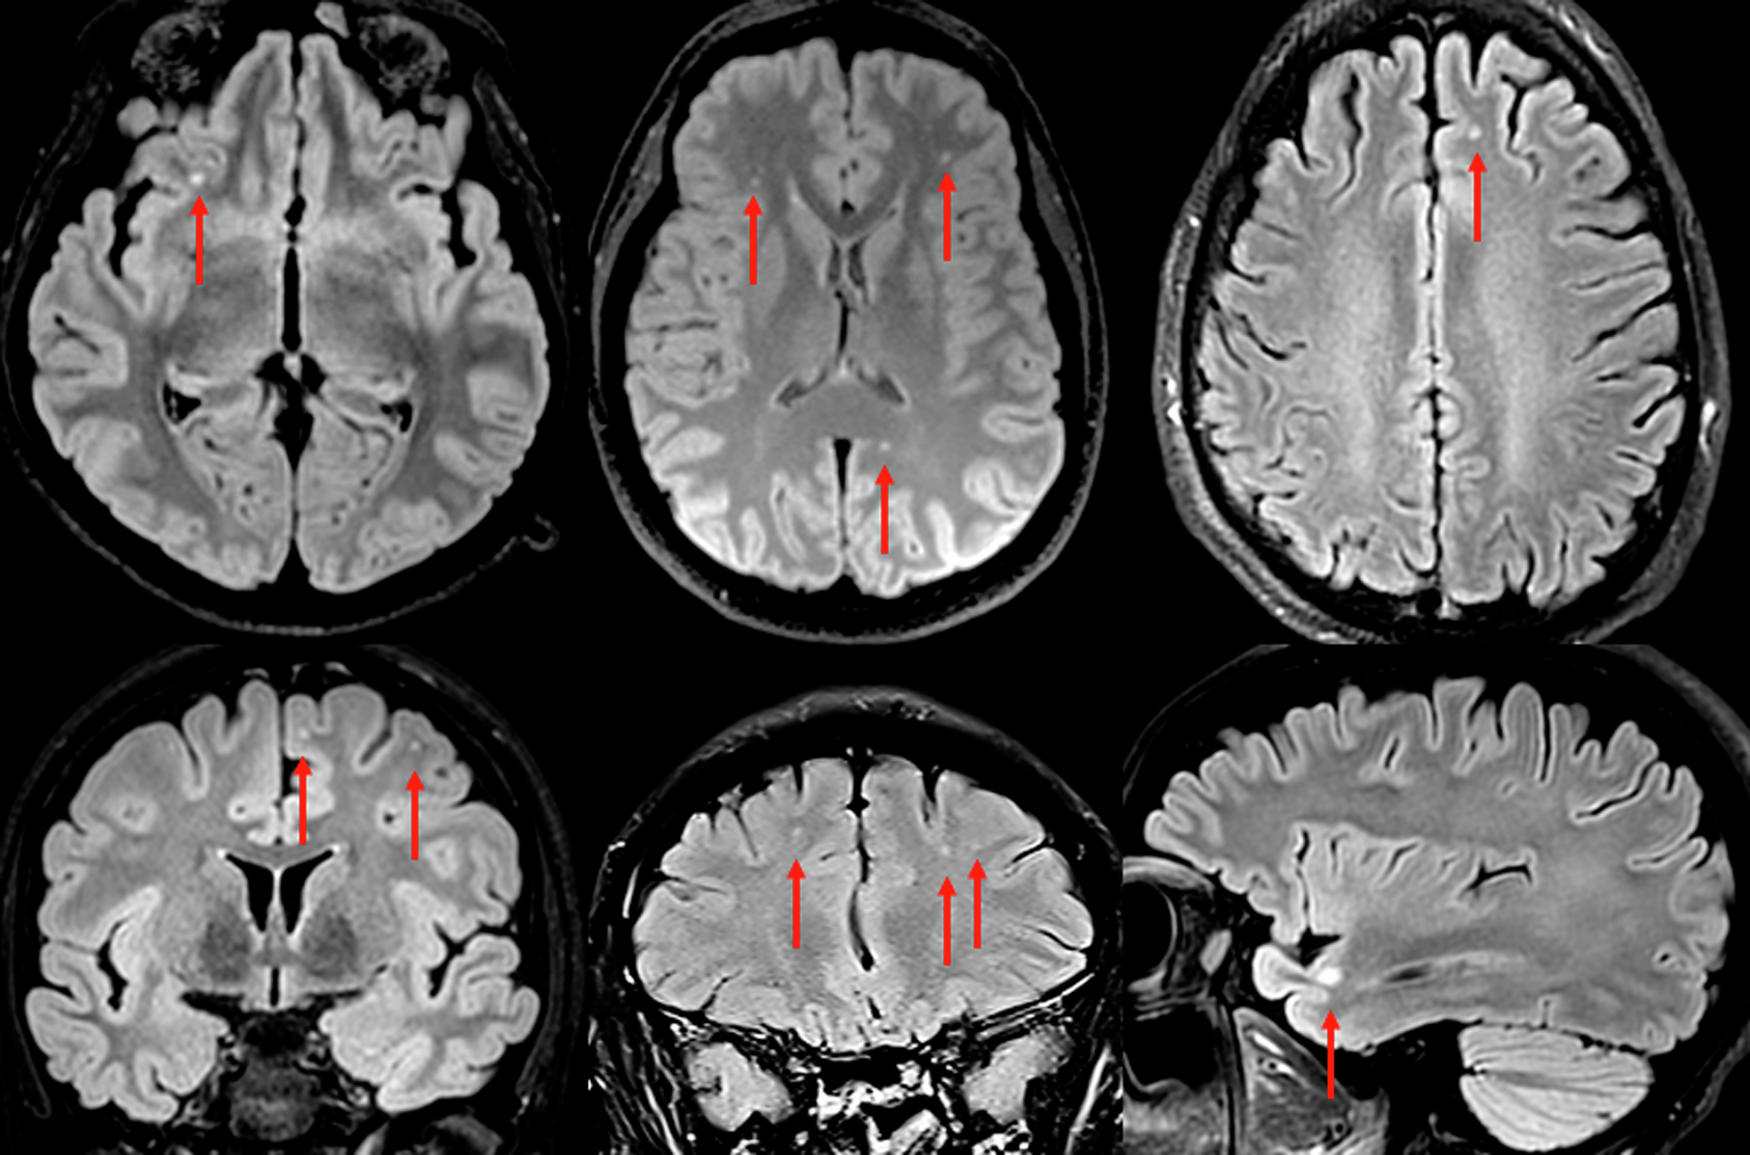

Fig. 1: FLAIR images from brain MRI in six representative cases.

All six cases have non-specific but distinct and well-demarcated spherical white matter changes. This was a common finding in the study, and more than expected for the age group. The most prevalent locations were deep white matter in frontal and parietal regions. The bottom right image shows a juxtacortical lesion in the temporal lobe. Juxtacortical lesions are rarely caused by small vessel disease, but rather associated with inflammation.